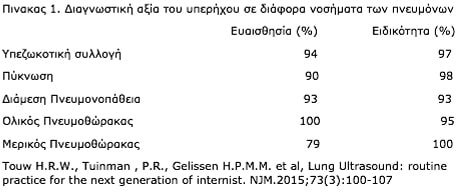

· Είναι εξέταση υψηλής διαγνωστικής αξίας για τις παθήσεις του αναπνευστικού: Μεγάλες πολυκεντρικές μελέτες έχουν τεκμηριώσει την υψηλή ειδικότητα και ευαισθησία του υπερηχογραφήματος πνευμόνων για συγκεκριμένα νοσήματα του αναπνευστικού ως παρόμοιας διαγνωστικής ακρίβειας ακόμα και με την αξονική τομογραφία θώρακος η οποία αποτελεί σήμερα εξέταση αναφοράς (gold standard) για την απεικόνιση του αναπνευστικού συστήματος, (πίνακας 1).